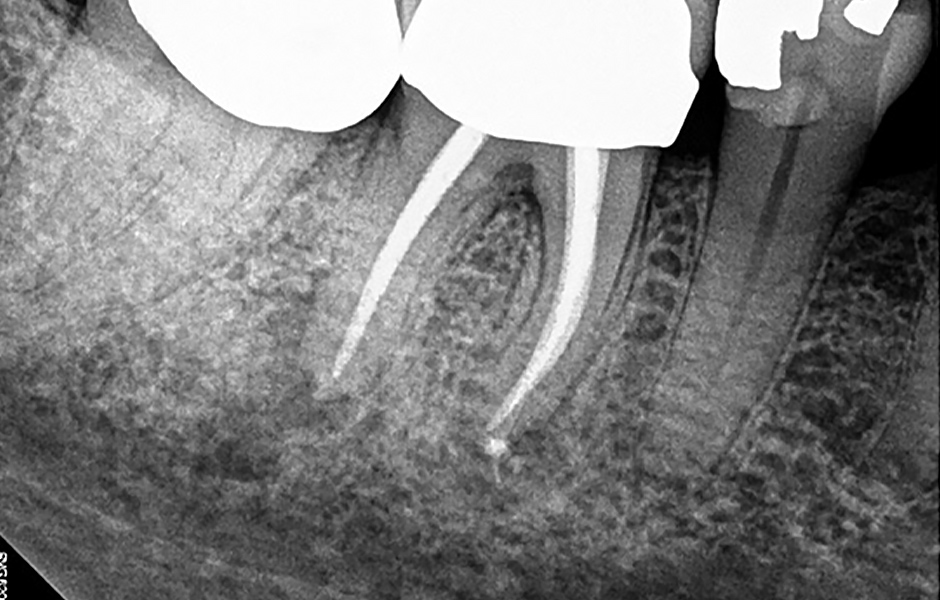

Pro radiologickou diagnostiku byl pořízen periapikální (PA) rentgenový snímek (obr. 1) a CBCT snímek s omezeným zorným polem (obr. 2a–d). Předchozí endodontické ošetření zahrnovalo zaplnění tří kanálků s nedostatečnou hustotou výplně v apikální třetině meziálních a distálních kořenů. V oblasti apexů meziálních (3 × 3 mm) a distálních (3 × 5 mm) kořenů byla patrná periapikální projasnění. CBCT (obr. 2a–d) potvrdilo nezaplněný distolingvální (DL) kanálek a možný střední meziální (MM) kanálek; koronální CBCT řez meziálního kořene (obr. 2c) také naznačuje přítomnost apikální delty spíše než jediného apikálního foramenu. Nebyly zjištěny žádné známky prasklin či fraktur.

Obr. 1: Předoperační PA rentgenový snímek zubu 46.